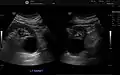

Renal ultrasonography of a simple renal cyst with posterior enhancement.

Renal cyst as seen on abdominal ultrasound